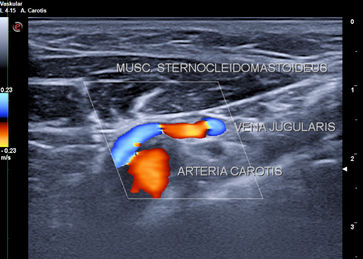

Goldstandard ist die Punktion der rechten Vena jugularis/anonyma supraklavikulär nach oder unter sonographischer Kontrolle. Die Sonographie muß Lagevarietäten klären und Thrombosen nach früherer Katheterisierung ausschließen.

Die Vena jugularis/ Vena anonyma kann nach Yoffa zwischen medialem und lateralem Kopf des Musculus sternocleidomastoideus von ventral punktiert werden oder horizontal von lateral. Diese Methode wurde 1972 von den amerikanischen Herzchirurgen Garcia, Mispireta und Pinho nach ausführlichen anatomischen Präparationen als einfachster und ungefährlichster Zugang beschrieben. Das Zielgebiet, der Zusammenfluß von Vena jugularis und Vena subclavia zur Vena anonyma ist so groß, dass die Punktion auch ohne Sonographie immer beim ersten Stich gelingt.

Die Punktion von ventral kann unter realtime Sonographie mit einem Standardschallkopf wegen des geringen Abstands zur Clavicula nur in der kurzen Schallachse erfolgen, wobei die Nadel nur abschnittsweise sichtbar ist. Mit dem kleinen 22 MHz Fingerschallkopf aus der Rheumatologie ist auch eine Punktion in der langen Schallachse möglich.

Die in der Anästhesie verbreitete Punktion der distalen Vena jugularis ist komplikationsträchtig und sollte vermieden werden. Normalerweise liegt die Vena jugularis lateral der A. carotis.

Bei der schädelnahen Punktion muß der Kopf nach links gedreht werden, weil sonst das Kinn im Weg ist. Dadurch rotiert die Vene vor die Arterie und das Lumen wird schlitzförmig.